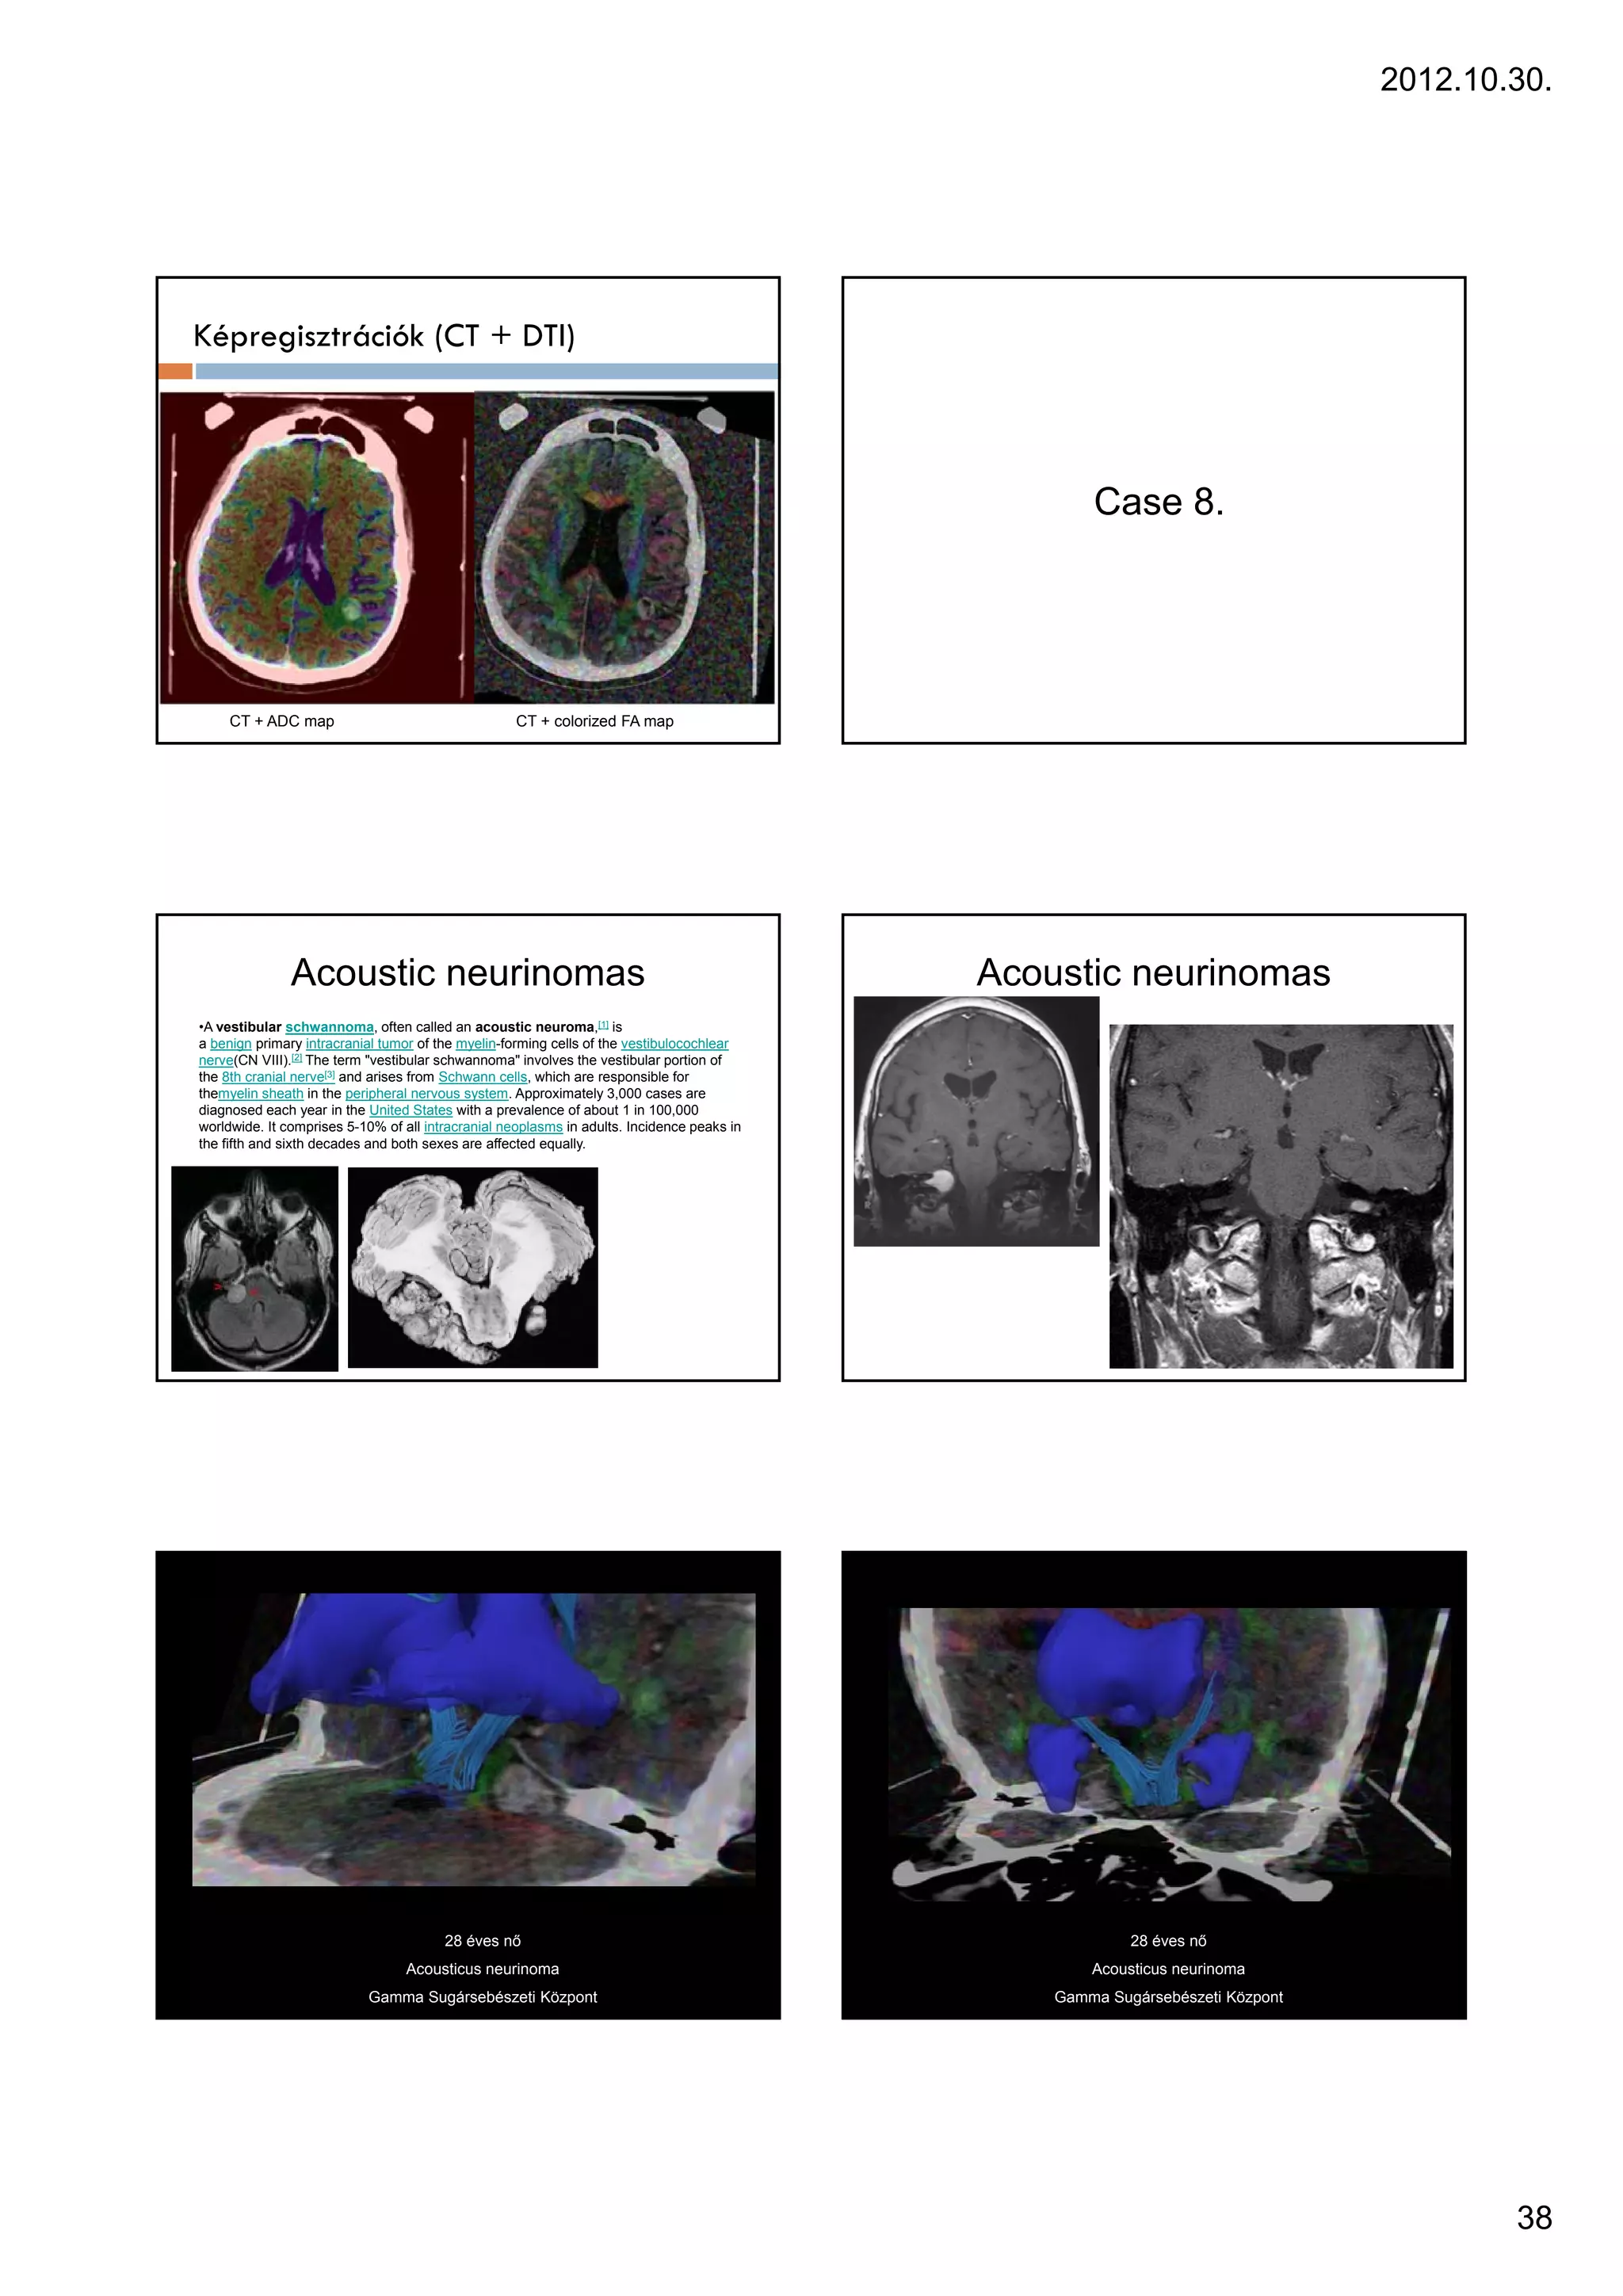

Képregisztrációk (CT + DTI)

CT + ADC map                                   CT + colorized FA map

Acoustic neurinomas                                                          Acoustic neurinomas

•A vestibular schwannoma, often called an acoustic neuroma,[1] is

a benign primary intracranial tumor of the myelin-forming cells of the vestibulocochlear

nerve(CN VIII).[2] The term "vestibular schwannoma" involves the vestibular portion of

the 8th cranial nerve[3] and arises from Schwann cells, which are responsible for

themyelin sheath in the peripheral nervous system. Approximately 3,000 cases are

diagnosed each year in the United States with a prevalence of about 1 in 100,000

worldwide. It comprises 5-10% of all intracranial neoplasms in adults. Incidence peaks in

the fifth and sixth decades and both sexes are affected equally.

28 éves nő                                                       28 éves nő

Acousticus neurinoma                                              Acousticus neurinoma

Gamma Sugársebészeti Központ                                         Gamma Sugársebészeti Központ